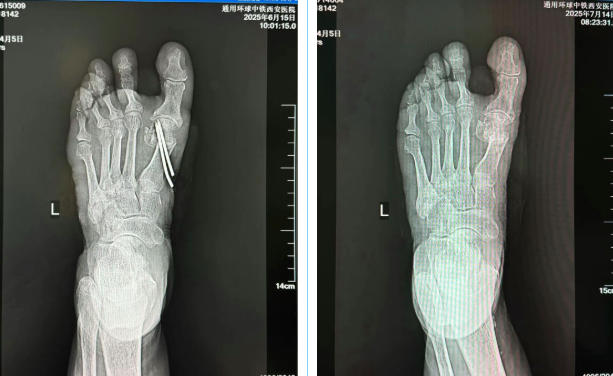

术前影像图

术后影像图

吕红兵完善相关检查发现,患者左足踇趾挤压第2趾,第1跖骨头处压痛明显,诊断为左足第一跖趾关节炎、左足踇囊炎,系重度踇外翻,拟行手术治疗。